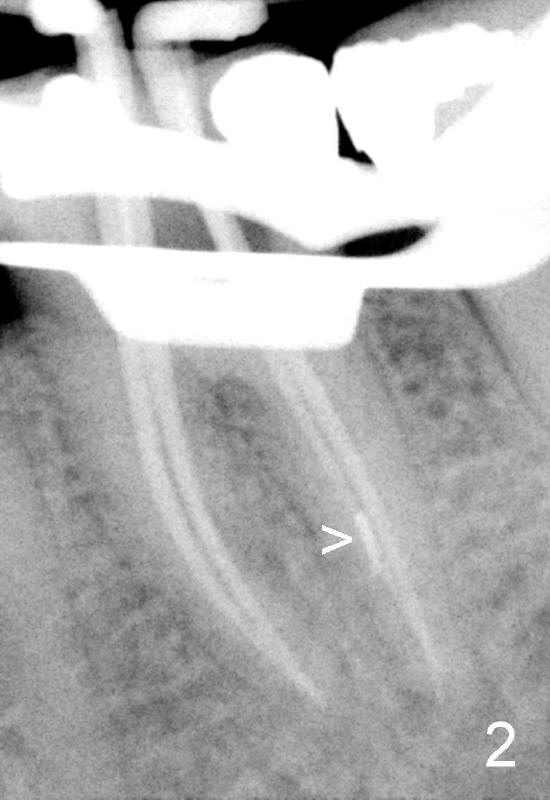

其实本文题目是如何让植牙病人找上门。冯女士四十二岁,四五年前因左下六牙痛第一次登门就诊,X光片显示牙根很长(图一),近中根根尖有阴影(>),那根牙根弯曲,总之,稀里糊涂开始根管治疗,结果有四根根管(图二),又长又弯,远中舌侧根断针(>),但是重新通过,辛辛苦苦完成根管治疗时才发现远中舌侧根弯弯曲曲(图三箭头,黑色箭头指向原来断针)。这些年来这颗牙齿没问题,但是左上七号牙老是发炎,全景片表明那颗牙齿根分叉处有阴影(图四箭头),一直劝她拔牙,植牙,上个月她终于同意拔牙,准备年底植牙。只有认认真真为病人解决痛苦,才能赢得他们信任,一旦他们需要进一步治疗,也会乐意开口。根管治疗做起来吃力,但是最能显示赤胆忠心。做好根管治疗是开展植牙第一步,愿意保留牙齿的人,视牙如金,如果我们尽力而保留不了,他们还是愿意更上一层楼;轻易拔牙的病人很少后来回来做植牙。